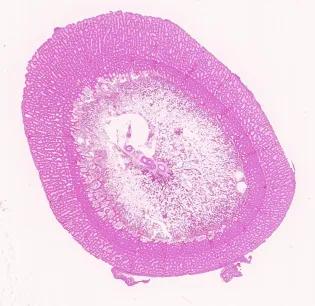

Whole transverse section of fast growing broiler chicken tibia, H&E stain.